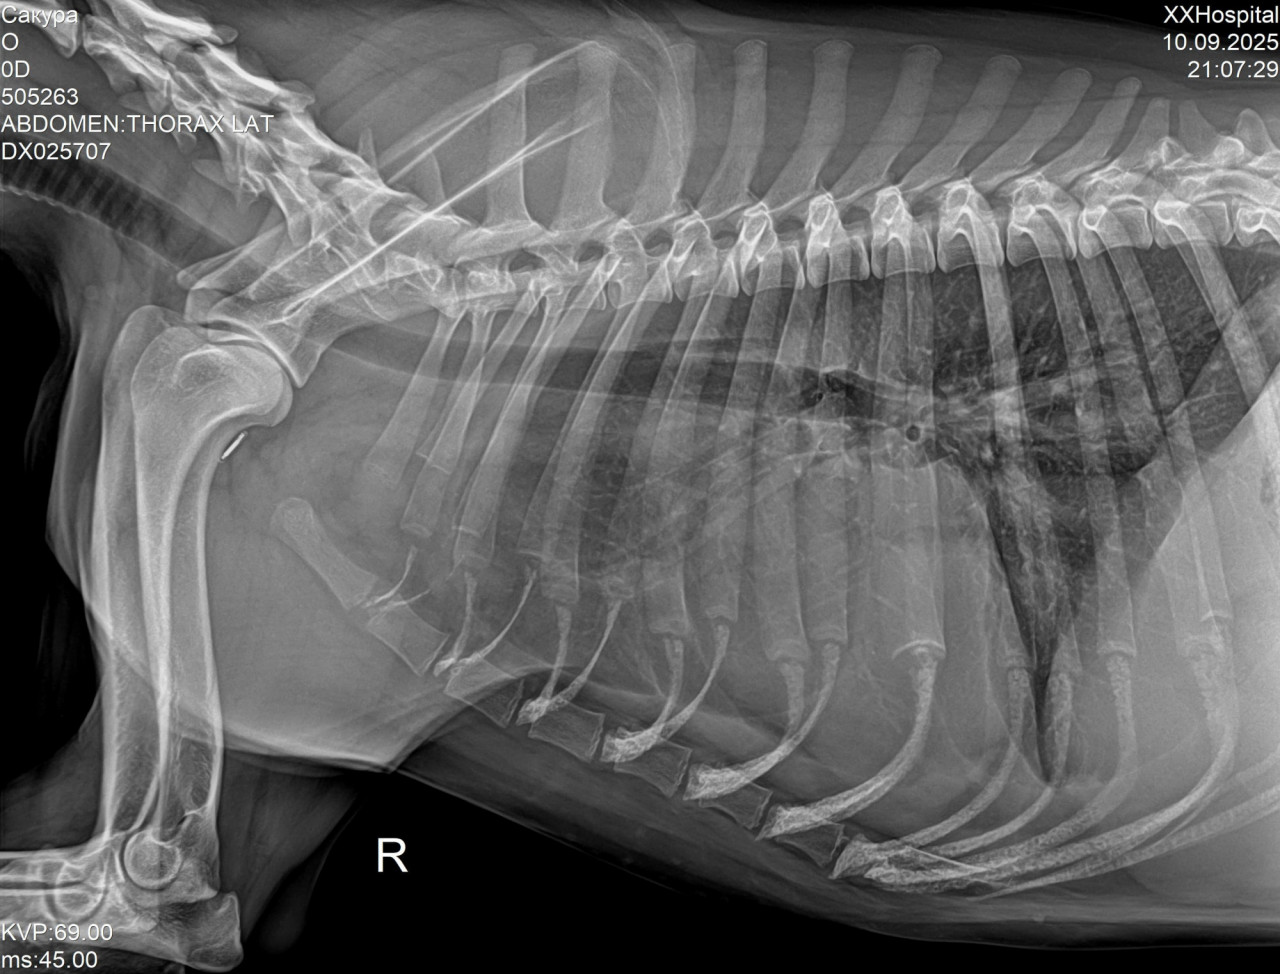

Добрый день, подскажите пожалуйста что по снимку у собачки, напугали каким то заворотом легкого

Здравствуйте. По снимкам видна неоднородность в лёгких, но поставить диагноз «заворот доли лёгкого» только по рентгену нельзя т.к требуется клиническое обследование и  КТ. Обязательно покажите результаты ветеринарному пульмонологу.

Была пневмония, скажите пожалуйста очень серьезное что то по снимку или это вариант нормы после пневмонии

После пневмонии на рентгене могут сохраняться остаточные изменения и это вариант нормы, но для точной оценки нужно сравнение с предыдущими снимками. Что касается сердца, то по рентгену его форму и размеры можно лишь предположить, окончательно оценить геометрию можно только на ЭКГ и ЭхоКГ.